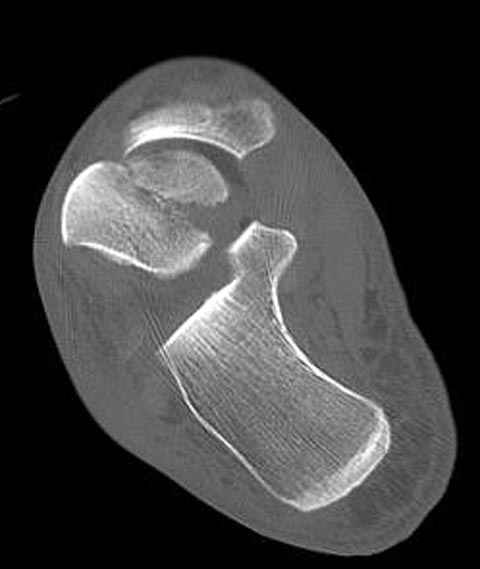

Уважаемые участники русского Ортофорума, поздравляю всех со всеми прошедшими праздниками: Новым годом, Рождеством, Hanukkah, Kwanzaa, желаю участникам всего наилучшего и здоровья.Повреждение таранной кости.Больной 81г автоавария, повреждение таранной кости, здесь снимки. Какие рекомендации?Djoldas Kuldjanov, MDDepartment of Orthopedic SurgerySt. Louis University Medical Center

В декабре у меня был пациент с политравмой и аналогичным повреждением тарана с подвывихом в таранно- ладьевидном суставе, единственное отличие - отломок головки тарана был меньше по размеру и фрагментирован, поэтому его фиксация была невозможна.

Для доступа к задне-медиальному суставному фрагменту я выполнил косую остеотомию внутренней лодыжки у её основания -получается хороший доступ к голеностопу, адекватный обзор и возможность восстановить суставную поверхность. фрагмент фиксировал двумя 3,5 мм спонгиозными винтами с неполной резьбой, *утопив* головки винтов в кость. Аналогичная фиксация и двумя тягловыми винтами и внутренней лодыжки. \в качестве альтернативы для

фиксации фрагмента тарана можно было бы использовать и герберт винты, но по организационным причинам :-(( набора не оказалось под рукой).

Вывих в таранно-ладьевидном суставе удалось вправить с помощью Howard retractor, используя его в качестве рычага.Сегодня искал в рентген архиве

Повторный осмотр назначил через 2 мес с момента операции. Отдаленных наблюдений такого подхода у меня нет( достаточно редкий тип повреждений таранаHawkins II), но наблюдения в ближайшем послеоперационном периоде выглядели вполне прилично, на мой взгляд.